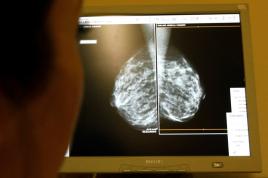

الفحص الروتيني يمنع نحو 1300 حالة وفاة بسبب سرطان الثدي سنوياً في المملكة المتحدة غير أن فحوص الثدي الشعاعية المدعومة بالذكاء الاصطناعي قد تنقذ أرواحاً أكثر

سرطان الثدي